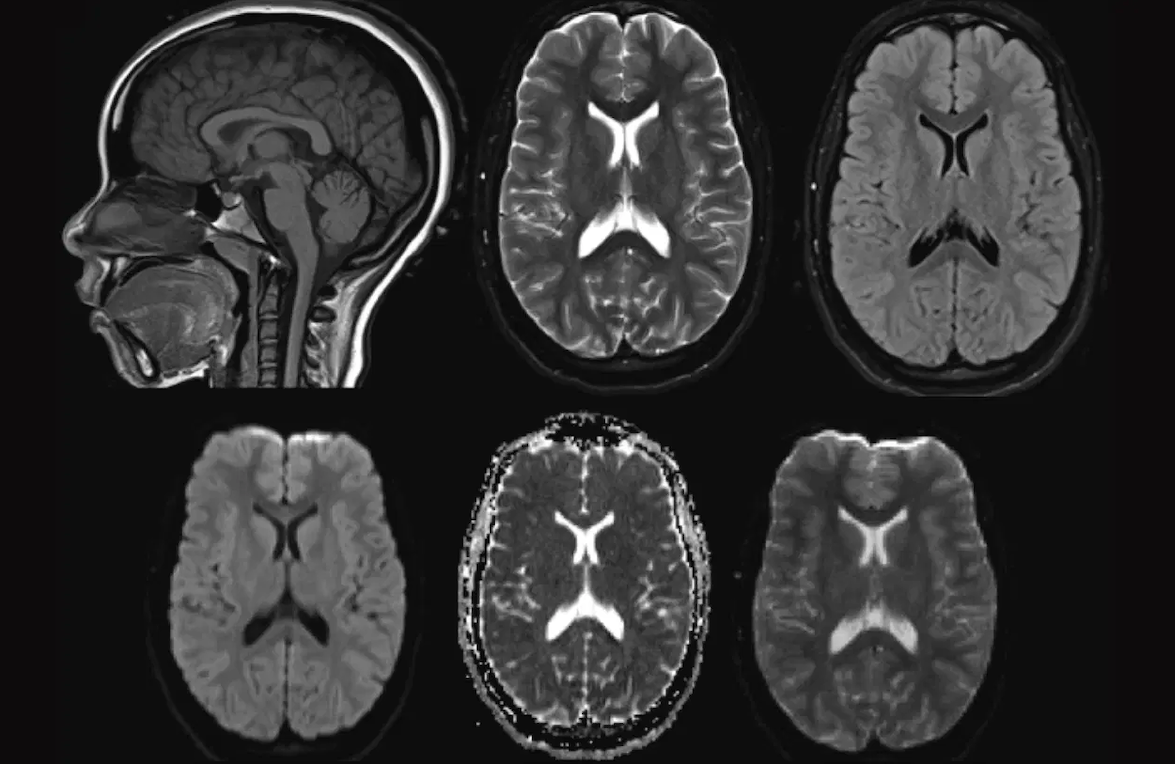

Just as elite athletes willfully expose themselves to stress—learning to thrive amidst fatigue and imperfect conditions—so too must we reconsider how we approach skill-building in other areas of life, especially listening. This becomes even more apparent in difficult conversations. When someone gets louder or more emotional, it usually signals they don’t feel heard—a moment that triggers deeper, instinctive reactions from the brain, making us feel threatened or unsafe in the exchange. The discussion quickly becomes less about the content and more about the pain of feeling disconnected. In these moments, our impulse is often to withdraw or to try and restore order to the conversation, seeking comfort. But, much like the athlete who chooses to remain in the discomfort of fatigue for the sake of growth, the true listener willingly stays present in these imperfect, chaotic, and challenging situations. Inside the brain, something transformational occurs as we sit with the discomfort, when we choose to stay in an imperfect conversation. It can create a bonding process in the nucleus accumbens (NAc), which regulates motivation and emotional responses. The discomfort we experience while listening can strengthen our connections with others, allowing us to be more vulnerable and intrepid. This is an area that is part of the brain circuitry that is critically involved formulating an addiction. But also a connection with someone else, especially the individual we are having that difficult interaction with. Allowing us to be comfortable with that person in order to create a stronger connection. In a male’s brain Vasopressin and in a female brain often Oxytocin, a hormone distinct molecules; these peptides and their receptors [OT receptor (OTR) and V1a receptor (V1aR)] are released in ventral pallidum, a component of the limbic loop of the basal ganglia, a pathway involved in the regulation of motivation, behaviour, and emotions, both in males and females. As we navigate an imperfect conversation's ups and downs, and listen. These molecules let us feel more safe by regulating how we are experiencing that conversation through our brain and we begin to understand the other individual in a way we haven’t before. This allows us to listen more openly within more difficult conversations not only with that individual but also with others, we expand our listening in conversations. We start to recognize and understand our vulnerabilities, just like athletes we hone in on the moment. Being aware of and acknowledging them as a source of strength. It allows us to move through the body, be at conscious choice, and create from our vulnerabilities. Vulnerability is not weakness, because vulnerability is about uncertainty, risk and emotional exposure. Vulnerability is daring and our nervous system doesn’t like it.  It likes what we can predict because it will be more adapted to respond. But just like athletes, if we stay at that level our body can’t respond to new stressors. As our nervous system is much more dominant and in control than our muscles. This is why athletes engage in meticulous and rigorous boring steps to penetrate their nerve reflexes, stacking them on top of each other, to help them transform their nervous system. Every aspect of skill we try to improve requires hard work and listening should not be any exception. The problem is we can’t build a system around listening with the same metrics as running 100 meters. The reliance to focus on listening from a conscious point of skill, makes our nervous system become an afterthought and invisible to our standards for what we identify as good listening. Learning to listen well begins with understanding what type of listener you are and that starts with your nervous system. We can train listening to be instinctual just like how elite athletes train their muscles through a diversity of exposures. Whereas we can train through sound, with different frequencies for our brain to be more fluid in connecting. As sound influences us in so many unimaginable ways, the flow of running water, birds on the morning street and soft rumbling winds create a typically gentle and rhythmic soothing for us. This is because our brains are wired to recognize these sounds as safe. It is ecology in motion. It is nature making itself heard. What isn’t safe to our brains are sounds we can’t hear, like silence. Some silence doesn't have frequency and this triggers our nervous system. This also triggers our auditory cortex too, as I learned working with born deaf children. Losing the capacity to hear doesn’t mean you’re not listening. Hearing in silence actually activates the auditory cortex, showing that the brain responds to the absence of sound much like it does to actual sounds. This heightened alertness may explain initial unease but also stimulates beneficial processes such as neurogenesis (the growth of new brain cells). Your nervous system is always listening, because it is the system that is responsible for keeping you alive and the communication within your body. It doesn’t understand a verbal language and therefore we have to learn to speak the language of the nervous system. Which is somatics, internal physical sensations, perceptions, and experiences of the body, an embodiment, in order to actually make change to it. We have to build our capacity within triggering our discomfort to our nerves. When it comes to doing this with our listening this appears confusing if we’re focusing on listening from primary being about hearing sound. Instead of focusing on vulnerability, something that has an energetic charge to it and if our nervous system doesn’t have an experience or reference point of that yet while learning, it overwhelms our system and body to get out. When I say “vulnerability is energy”, it might be hard to resonate or understand what that actually means, but in order to know how? We have to look at our brain through an MRI machine. The way an MRI works is by using a powerful magnetic field and radio waves to generate images of the body and of the brain.This machine uses these powerful magnets that align the protons in our body’s water molecules. It then sends radio waves through the body, which knock protons out of alignment. When the radio waves are turned off, the protons realign with the magnetic field releasing energy in the process, the energy is detected by the machine and a computer then processes that energy into a detailed image. When our brain experiences vulnerability we can see brain activity in the amygdala, a processing center for emotions, like fear. When our body experiences vulnerability it produces more oxygen. This is to ensure that oxygen is available to support heightened activity levels, for releasing energy in the body. Deoxyhaemoglobin is a paramagnetic molecule that creates an inhomogeneous magnetic field in its immediate vicinity that increases T2; a tissue can be characterized by two different relaxation times – T1 and T2, at rest, tissues use substantial fraction of the blood flowing through the capillaries so venous blood contains an almost equal mix of oxyhaemoglobin and deoxyhaemoglobin. During exercise or through discomfort, however when the metabolism is increased, more oxygen is needed and hence more is extracted from the capillaries. The brain is very sensitive to low concentrations of oxyhaemoglobin and therefore the cerebral vascular system increases blood flow to the activated area. What these processes of vulnerability allow us to uncover with our body and brain, is just how profound the absence of sound can be an integral part of reconfiguring our nervous system. Something as simple as low frequencies can be our building blocks to getting there, as one research paper in 2022 surrounding speakers underscores with undetectable very-low frequencies at live concerts. As humans our audio spectrum range spans from 20 Hz to 20,000 Hz( hertz), this range is our capacity to hear sound. What researchers of this paper discovered was that these low undetectable frequencies actually increase individuals to dance more. As low pitches confer advantages in perception and movement timing, and elicit stronger neural response. Researchers had individuals provide consent to have motions capturing marker headbands on their head. During the concert, the speakers only (low frequency or what they called: VLF) would be turned off and on, this resulted with more motions to dance in the low range ( 8-30 Hz they tested) Where the participants experienced a pleasurable urge to move. A large number of neurons began firing exactly in sync with the beat, which resembled the low frequencies that were played, training the neurons in their brain to match to that rhythm. This suggested low frequency sounds shape neural representation of the cortical level by boosting selective neural locking in our brain to a beat. In other words researchers are starting to realize that the sounds we can't hear—or struggle to hear—can have a greater impact on us than the ones we can. While silence alone isn't the key to improving our listening, it is an important first step in reconnecting with our nervous system. In fact some silence is detrimental and being exposed to it for too long can harm you. “You can’t change anything with silence” is what Allyson Felix, one of the most decorated athletes in history: a six-time Olympic gold medal winner and an 11-time world champion, said in her 2019 article in the New York Times. Allyson's experience of silence reached a breaking point, she wasn’t enduring the status quo around maternity. Where athlete mothers were punished for their pregnancy. She provoked huge changes by breaking her silence, forcing big brands like Nike who sponsor female athletes and others to change female athlete’s rights surrounding pregnancy. As a mother, she continues to grow and has learned that being kind to her body needs to be her ultimate priority. “Now that I’ve been in this sport for so long, taking care of my body is number one. I place such high importance on that, listening to my body” she shares in an interview. The process of listening, much like the performance of elite athletes, is not about striving for perfection or controlling every aspect of our environment. Instead, it is about learning to work within discomfort, embracing imperfection, and trusting our ability to respond effectively to what we cannot always control. Wyomia Tyus's story exemplifies how success comes not from eliminating external pressures, but from understanding and adapting to them—listening to one’s body, finding balance within chaos, and performing under pressure. Similarly, effective listening is not about perfect conditions or flawless execution; it’s about accepting the discomfort of imperfection and allowing ourselves to truly engage with what is being communicated, both through sound and silence. As we move beyond the mechanical act of hearing, we can begin to refine our listening skills by embracing the challenges that arise from external noise, internal distractions, and emotional discomfort. Just as athletes train to optimize their response to their own physical limits, we too can train our minds to be more present, resilient, and adaptable in our listening, recognizing that it is through imperfection that we unlock deeper understanding and connection.